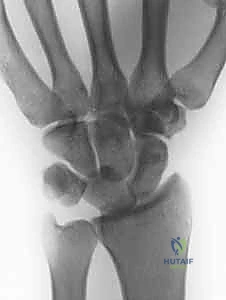

- Perilunate Dislocations: On PA, observe disruption of Gilula's lines and the lunate assuming a triangular, rather than trapezoidal, shape. On the lateral view, the concentricity of the "C's" (distal radius, lunate, capitate) is lost, indicating dorsal dislocation of the capitate from the lunate fossa.

Figure 3B: Lateral view showing dorsal dislocation of the capitate out of the lunate fossa.